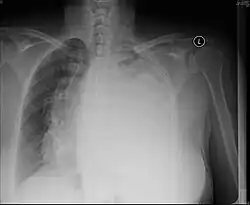

Chest x-ray demonstrating severe atelectasis or collapse of the right lung and mediastinal shift towards the right.

Atelectasis is the partial collapse of a lung that is reversible. There are numerous etiologies, including post-operative atelectasis, surfactant deficiency, mucus plugging, and foreign body aspiration. Notably, post-operative atelectasis is thought to be caused by general anesthesia administration. Collapse of the affected lung shifts mediastinal structure towards the same side and can be observed on chest x-ray or CT. Radiographic features include increased opacification of collapsed lung and/or tracheal shift.[14]